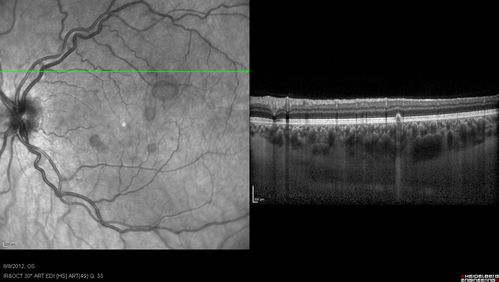

Punctate Inner Choroidopathy - PIC and Choroidal Neovascular Membrane - Right Eye - SD OCT

34-year-old woman with a change in vision in the right eye about eight days ago.  Her vision was hazy and she saw waviness in the vision.  She does have a history of aches and pains and she was diagnosed with Sjogren’s and 2 months ago she had some fevers and some sinus drainage and that went on for about two months.  She is a moderate myope.    OD 20/25, OS 20/20.